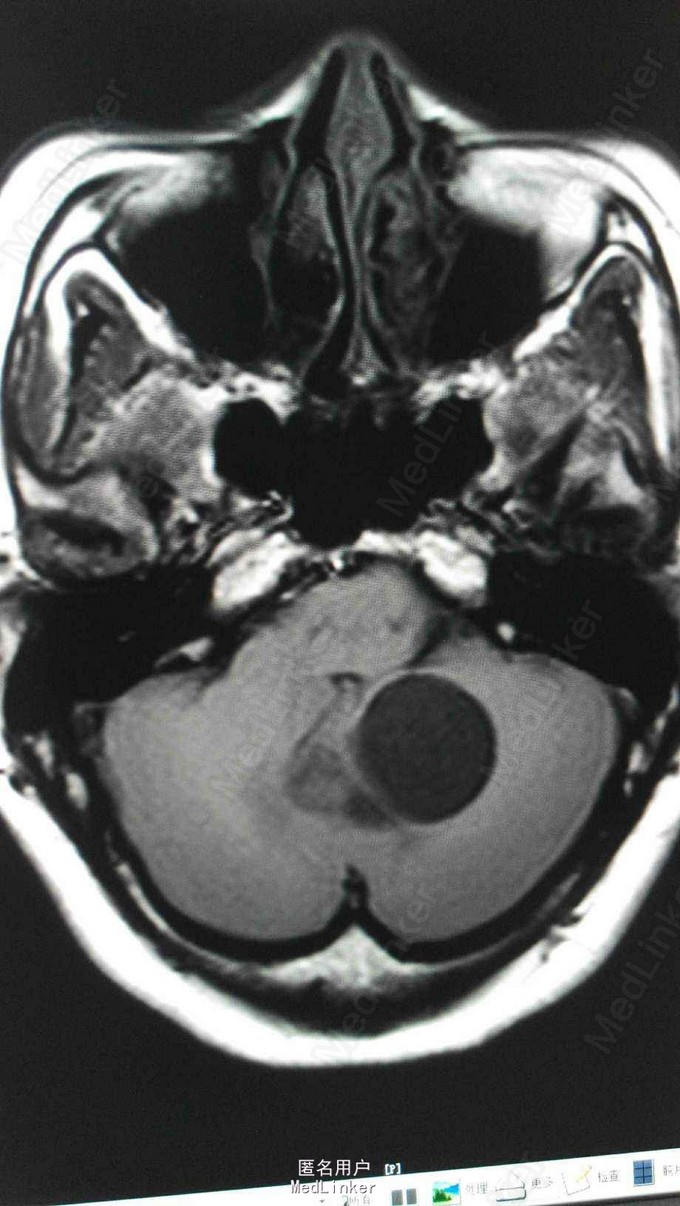

查体:T 36.5℃,P 81bpm,R 18bpm,BP 127/79mmHg;心肺腹及神经查体未及明显异常。 检查:三大常规、生化、凝血、乙肝、丙肝、梅毒、HIV未见明显异常。 头颅MRA:小脑蚓部占位,血管母细胞溜可能性大;左椎动脉颅内段局部轻度狭窄;左侧大脑前动脉A1段稍细。 腹部超声:右肾混合性占位性病变(中下极见一个大小约90*65*83mm的混合回声团,边界尚清,内回声不均,可见密集分布的无回声囊,呈蜂窝状);右肾局限性积液;胰腺内异常回声(多个大小不等的无回声囊,大者约12*11mm,边界清);双侧卵巢小囊(27*25mm(右)、25*25mm(左));肝、胆、脾未见明显异常;左肾、膀胱未见明显异常;双侧输尿管未见明显扩张;子宫未见明显异常。腹部增强CT ,胰腺多发囊性病变,右肾巨大占位,考虑肾癌。

VHL综合征 目前暂予完善相关检查及对症处理。